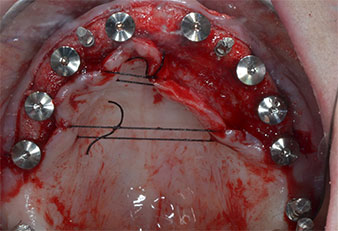

Implantatstabilität

Abb. 7: Die Implantatstabilität wird mit einem SmartPeg und dem W&H Osstell ISQ module ermittelt. Alle Werte befinden sich im mittleren bis hohen Bereich, mit einem Mindestwert von 69.

provisorische Implantate

Abb. 8: Nach Befestigung der Gingivaformer werden an den Positionen 18, 12, 22 und 28 provisorische Implantate eingesetzt.